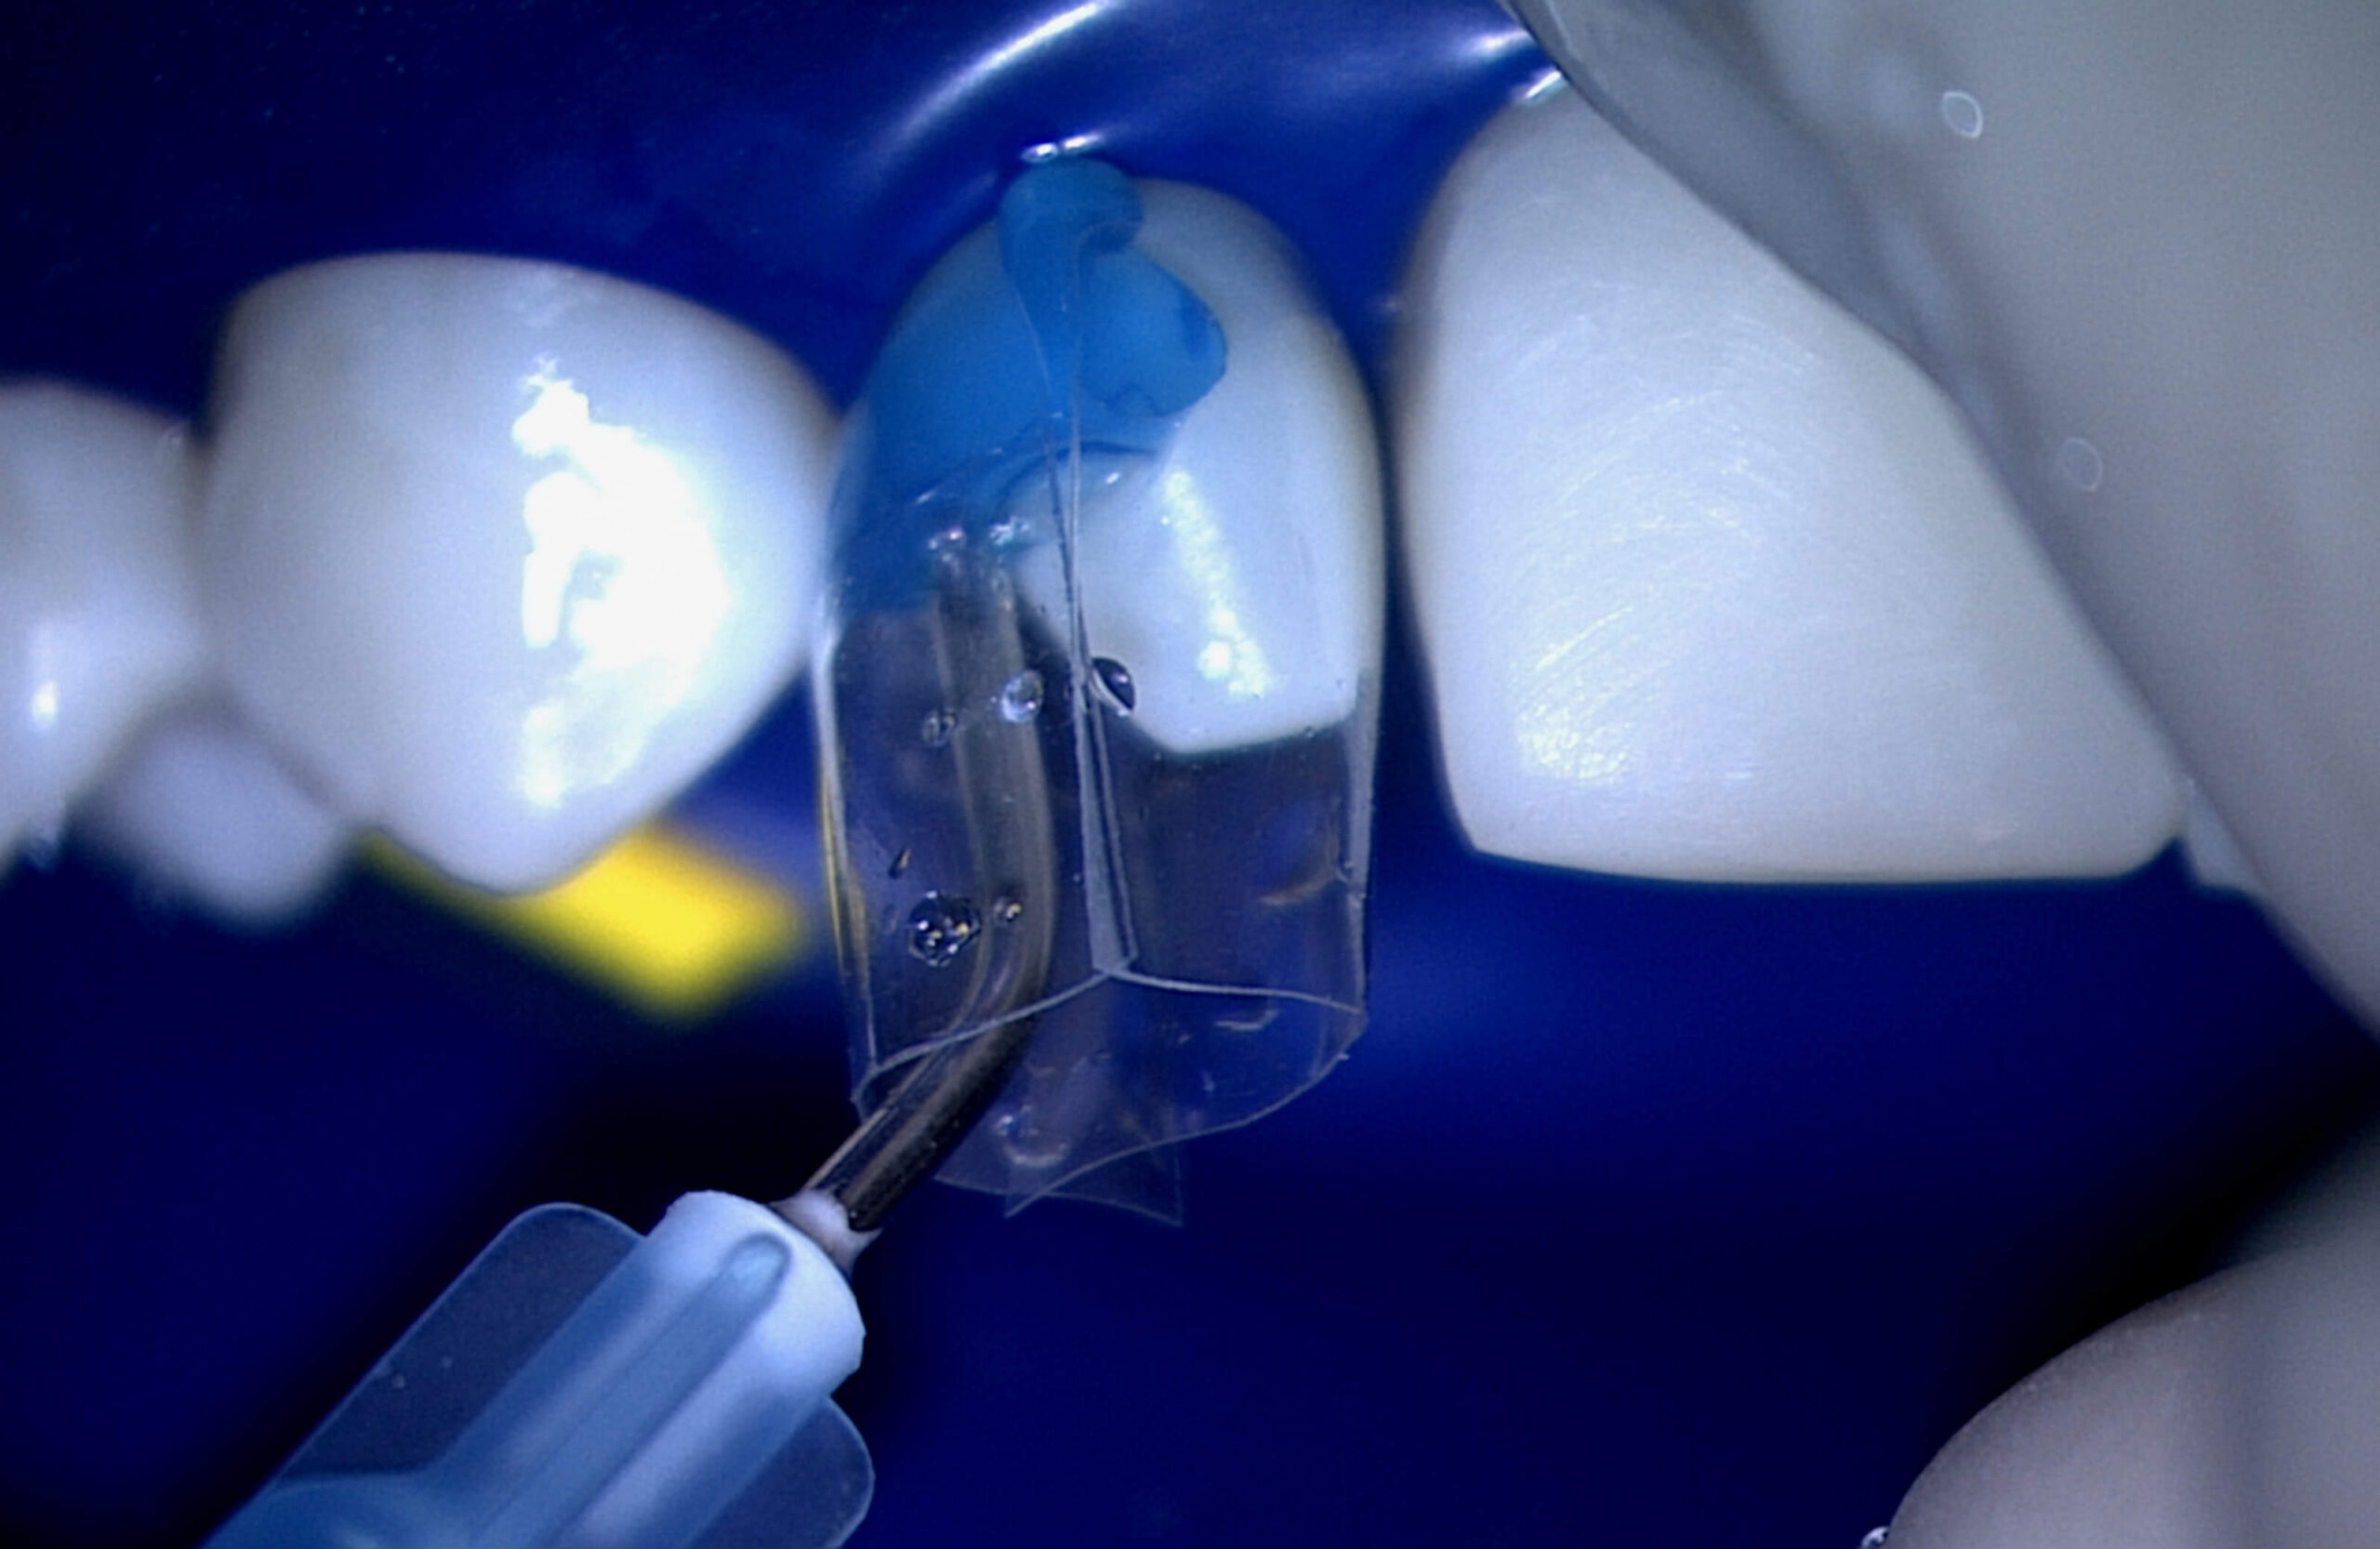

This video is in reference to the Dentistry Today article “Composite Over-molding for Aesthetics and Strength” in the August 2014 issue. This video series shows Dr. Clark using the Bioclear Matrix to build composite over-molding (sometimes referred to as composite veneers), on a teenage post orthodontic case.

Part 1 highlights:

The Original Anterior Matrices are used in this video (specifically the A-103).

This video is in reference to the Dentistry Today article “Composite Over-molding for Aesthetics and Strength” in the August 2014 issue. This video series shows Dr. Clark using the Bioclear Matrix to build composite over-molding (sometimes referred to as composite veneers), on a teenage post orthodontic case.

Part 2 highlights:

This video shows all the steps needed to close an open mid-line diastema, including the staged wedging technique.

Highlights: